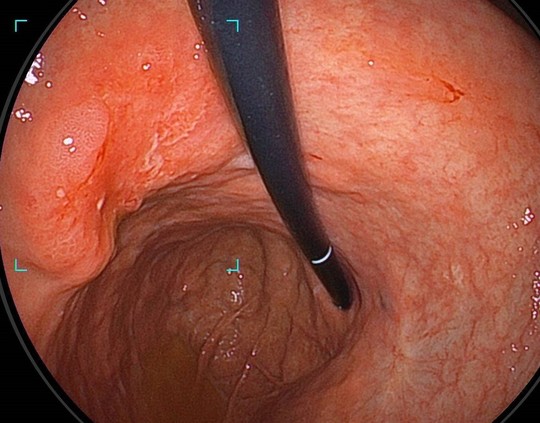

②反転観察でも確実に指摘

広い胃のなかでは反転し観察も行います。Scopeが写りこんでいても、確実に病変を捕捉していきます。